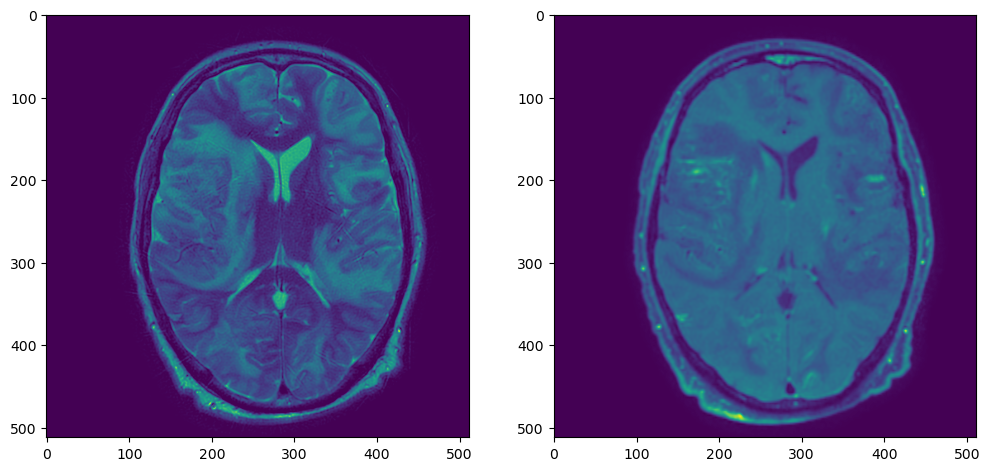

Для наглядности я взял T1 с контрастным усилением, SWI и T2. Т1-взвешенная серия нарезана сагиттально, SWI и Т2 – аксиально.

fig, axs = plt.subplots(nrows=1, ncols=3, figsize=(16,6))

axs[0].imshow(pydicom.dcmread(f'{resample_dir}/T1_CE/IMG-0003-00140.dcm').pixel_array, cmap='bone')

axs[1].imshow(pydicom.dcmread(f'{resample_dir}/SWI/IMG-0005-00046.dcm').pixel_array, cmap='bone')

axs[2].imshow(pydicom.dcmread(f'{resample_dir}/T2/IMG-0002-00030.dcm').pixel_array, cmap='bone')

Три серии